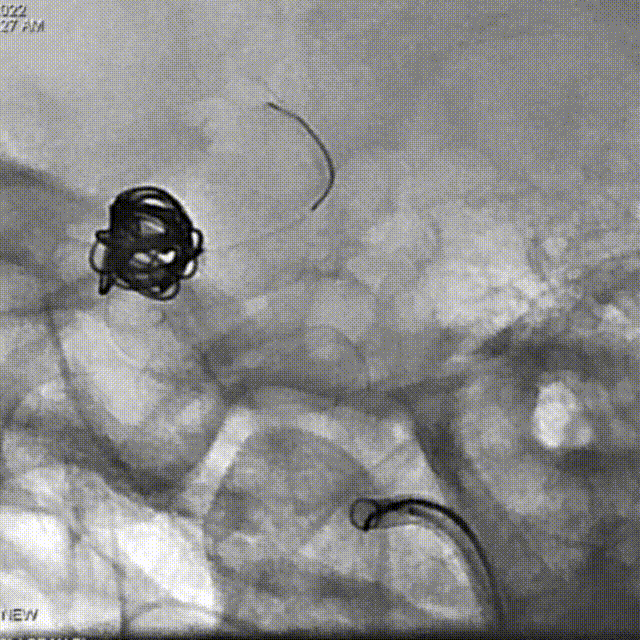

支架导管及弹簧圈微导管先后超选到位,其中弹簧圈微导管超选入远端眼动脉段动脉瘤内备用,根据测量结果,选用YonFlow®血流导向密网支架 4.5mm/30mm、弹簧圈9mm/40cm,先部分推出弹簧圈在动脉瘤内提供保护。再释放密网支架。

术后6个月造影随访提示动脉瘤完全愈合,载瘤动脉通畅。

4、该病例即刻造影显示血流重构满意,瘤腔内血流明显淤滞。术后六个月及12个月随访,均显示动脉瘤愈合,载瘤动脉通畅无狭窄。